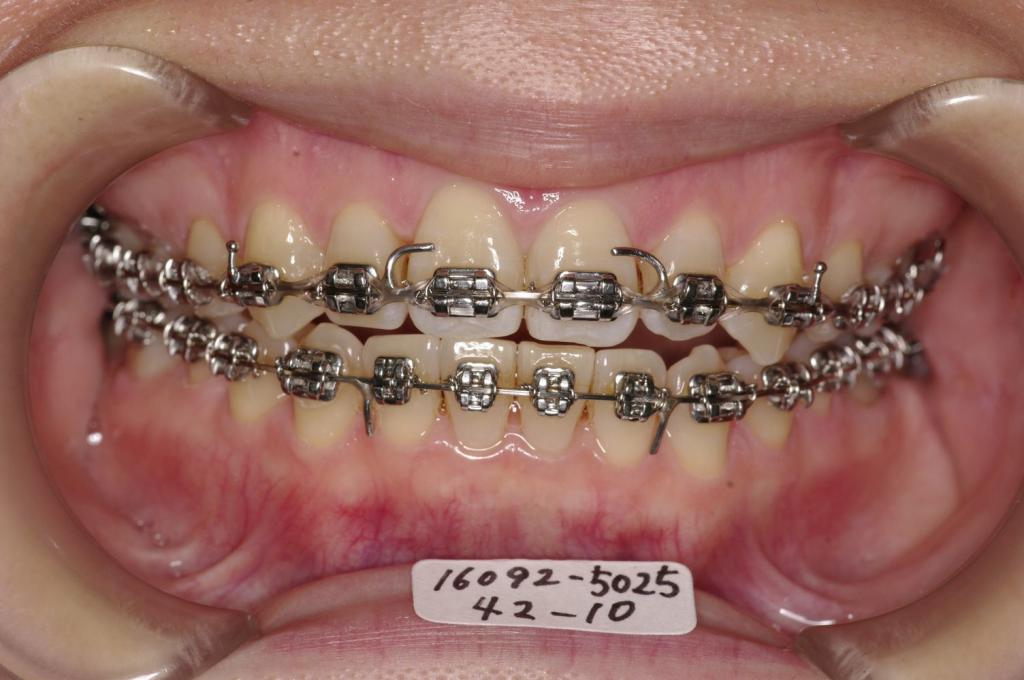

装置の種類及び治療法 診断:叢生

治療方法および装置:マルチブラケット装置

High pull J-hook headgear

抜歯:右上8 /左上7

右下8 /左下8

装置写真

治療前

歯並び・咬み合わせ・八重歯・乱杭歯の矯正治療前口内写真NO.1231